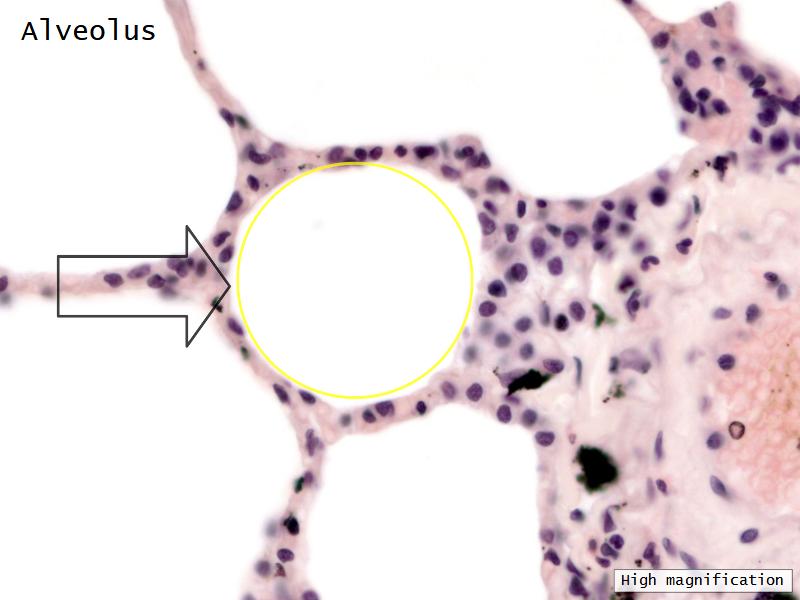

- Alveoli

Lungs

Components of the Blood-Air Barrier?